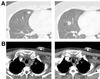

Adoptive T cell therapy, involving the ex vivo selection and expansion of antigen-specific T cell clones, provides a means of augmenting antigen-specific immunity without the in vivo constraints that can accompany vaccine-based strategies. A phase I study was performed to evaluate the safety, in vivo persistence, and efficacy of adoptively transferred CD8+ T cell clones targeting the tumor-associated antigens, MART1MelanA and gp100 for the treatment of patients with metastatic melanoma. Four infusions of autologous T cell clones were administered, the first without IL-2 and subsequent infusions with low-dose IL-2 (at 0.25, 0.50, and 1.0 x 10(6) unitsm(2) twice daily for the second, third, and fourth infusions, respectively). Forty-three infusions of MART1MelanA-specific or gp100-specific CD8+ T cell clones were administered to 10 patients. No serious toxicity was observed. We demonstrate that the adoptively transferred T cell clones persist in vivo in response to low-dose IL-2, preferentially localize to tumor sites and mediate an antigen-specific immune response characterized by the elimination of antigen-positive tumor cells, regression of individual metastases, and minor, mixed or stable responses in 8 of 10 patients with refractory, metastatic disease for up to 21 mo.